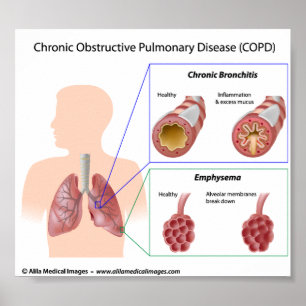

COPD Lung diseases diagram Poster

PriceCA$32.35